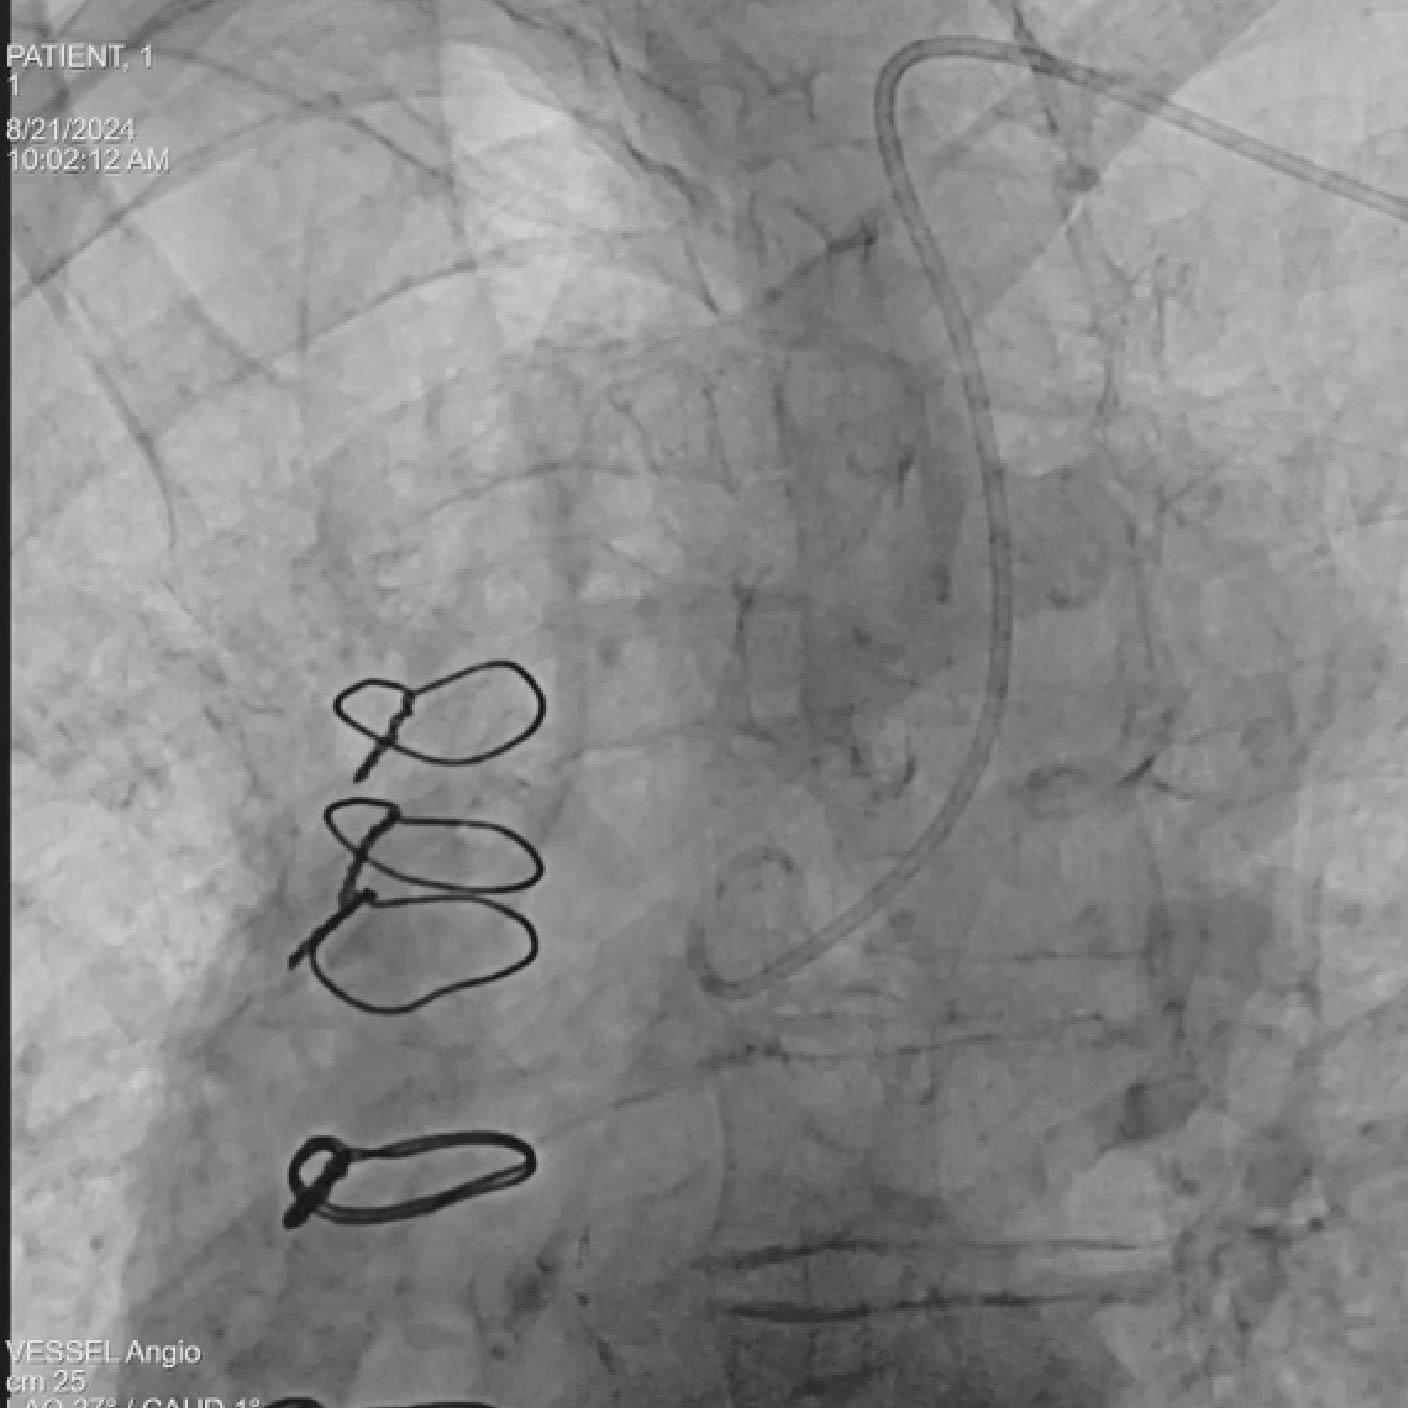

- Colocación y despliegue del dispositivo SENTINEL™

- Colocación del guía y del dispositivo con syngo Aortic Valve Guidance

Objetivo clínico: Soporte para la colocación de un dispositivo de protección cerebral como herramienta para mitigar el riesgo de accidente cerebrovascular embólico.

Soluciones y características seleccionadas: ARTIS pheno, Case Flows, Una combinación preestablecida de configuraciones (angulación, disposición de la pantalla, etc.), personalizada para la colocación del dispositivo SENTINEL™*, reduce las interacciones con el sistema. Con Case Flows, una única interacción del usuario reemplaza el ajuste de hasta 6 configuraciones del sistema³. syngo 2D/3D Fusion - Aplicación para superponer la anatomía de la arco aórtico basada en tomografía computarizada sobre fluoroscopia en vivo, para apoyar la navegación del dispositivo. Se ha demostrado que la guía por fusión reduce significativamente el tiempo de despliegue del dispositivo SENTINEL™* y el uso de contraste⁴.